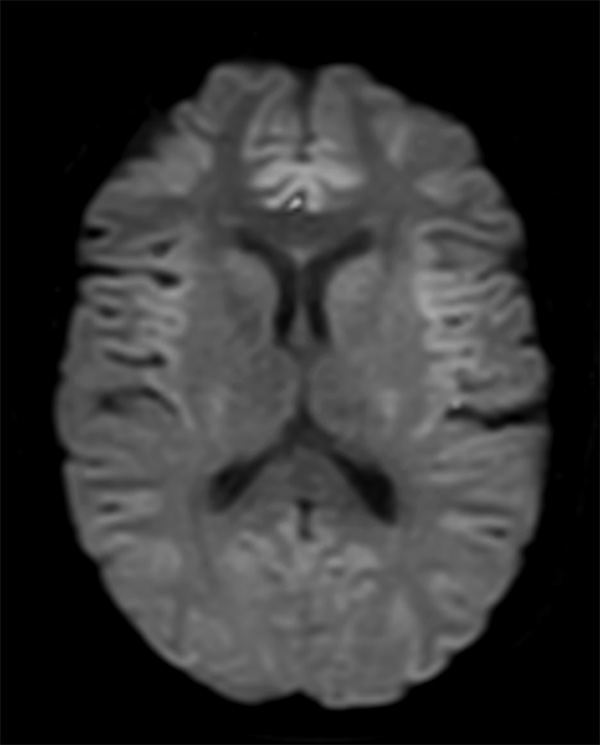

Comprehensive Brain imaging at 3.0T

• Clinical Application